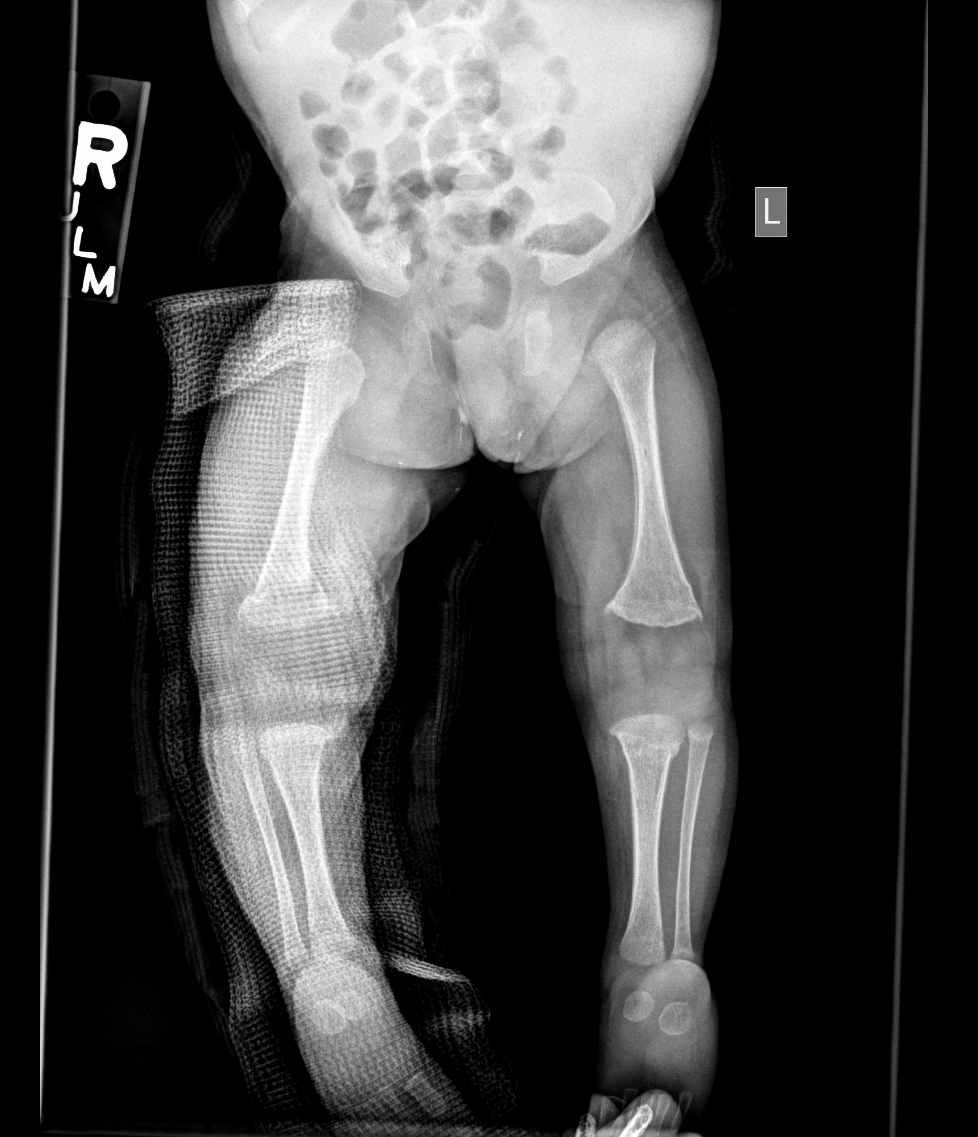

Info Images Findings Impression Reco/Acuity Case Images View Images / Launch Visage Case Notes History 2-month-old presents with decreased right arm movement, increased fussiness, and increased sleepiness for 2 days. Suspected non-accidental trauma. Exam Skeletal survey Prior Study none Dicom View Reference Material

Section 1 Submit Findings CB1550 Findings Skeletal Survey - Technique Check Skull AP/Lat Yes No Cervical and Thoracolumbar spine Yes No Chest X-Ray Yes No Ribs – Left/Right Oblique Yes No Abdominal X-Ray Yes No Pelvis with both hips Yes No Bilateral Humerus, Forearm, Hand Yes No Bilateral Femur, Tibia/fibula, feet Yes No Any additional lateral views of the extremities Yes No The exam is over or under penetrated. Yes No The exam may or may not be limited by overlying structures or soft tissues, body habitus, patient positioning, support devices, or motion. Yes No The area of concern is indicated by the patient, technologist, or care provider. Yes No The area of concern is included on the exam. Yes No Soft Tissues There is soft tissue swelling, indistinctness of fat/muscle planes, gas, or laceration in the area of clinical concern. Yes No There is an effusion, fat pad displacement, or fat fluid level. Yes No There is a radiodense or lucent foreign body. Yes No There are other densities, calcifications, post-surgical changes, or support devices in the soft tissues. Yes No Any support lines/tubes. Yes No Bone There is a break or interruption of the continuity of the cortical or cancellous bone. Yes No There is overriding of the trabeculae with apparent sclerosis. Yes No There is displacement of a fracture fragment. Yes No There is bowing of the bone in addition to the fracture at the apex of the bowed bone concerning for the greenstick. Yes No There is a spiral fracture of the leg concerning for toddler’s fracture. Yes No There is abnormal angulation or bulging of the cortical surface relative to the normal cortex which could be from a buckle or torus fracture. Yes No There is a displaced fragment which may be from avulsion by a tendon, ligament, or joint capsule or from a comminuted or other fracture. Yes No The stress trabeculae or other trabeculae of the cancellous bone are interrupted or otherwise abnormal. Yes No There is subperiosteal or endosteal reaction which could indicate a healing or subacute fracture or other abnormality. Yes No There is hard/soft callus formation. Yes No There is remodeling of the bone. Yes No There is a corner fracture or metaphyseal lesion that could be from nonaccidental trauma. Yes No There are multiple fractures of different ages. Yes No There are vertebral body/spinous process fractures. Yes No There are rib fractures. Location - posterior or lateral. Yes No There is scapular/sternal fracture. Yes No There are fractures of the digits. Yes No There are wormian bones. Yes No There are intrasutural bones. Yes No There is metaphyseal abnormality (lucencies, increased density, erosion) which may be from something other than injury such as stress, metabolic disease (e.g. rickets with loss or distortion of the zone of the provisional calcification), neoplasm (e.g. leukemia), heavy metals, inflammation, or infection. Yes No There are metaphyseal spurs. Yes No There are bony deformities involving multiple bones. Yes No The bones are gracile. Yes No There are non-healing fractures. Yes No There is/are focal or multifocal lytic/lucent, blastic/sclerotic or mixed density lesion(s) or other abnormality. Yes No Overall bone density is increased or decreased with or without thinning or thickening of the cortical or cancellous bone. Yes No Growth plates, ossification centers, apophyses The growth plate(s) is/are abnormal. Yes No There is widening of the physis from a fracture with or without displacement of the epiphysis (Salter-Harris I). Yes No There is a fracture through the physis which then extends into the metaphysis with or without angulation or displacement (S-H II). Yes No There is a fracture through the physis which then extends into the epiphysis and is intra-articular, with or without angulation or displacement (S-H III). Yes No There is a fracture through the metaphysis, physis, and epiphysis which extends into the joint space with or without angulation or displacement (S-H IV). Yes No There is narrowing of the physis from a compression fracture (S-H V). Yes No The apophysis, epicondyle, secondary ossification center, or accessory ossicle is displaced or otherwise abnormal. Yes No The ossification centers are underdeveloped. Yes No Joints and alignment There is an effusion, fat pad displacement, or fat fluid level. Yes No The epiphysis or subchondral bone is fractured, interrupted, flattened, compressed, impacted, displaced, or otherwise abnormal. Yes No There is an intra-articular loose body or chondrocalcinosis. Yes No The joint is widened, narrowed, dislocated, malaligned, or incongruent. Yes No There is pseudoarthrosis. Yes No Other findings There are developmental changes or other anatomic variants or other existing conditions that may or may not be contributing to symptoms which can or should be further evaluated non-emergently or are otherwise incidental. Yes No The remainder of the exam is abnormal for age. Yes No The lungs show focal airspace opacity. Yes No There is pneumothorax. Yes No There is organomegaly. Yes No There is intra-abdominal calcification. Yes No There is displacement of the bowel loops. Yes No There is free intraperitoneal air. Yes No The bowel loops are dilated/obstructed. Yes No There is paraspinal soft tissue abnormality. Yes No